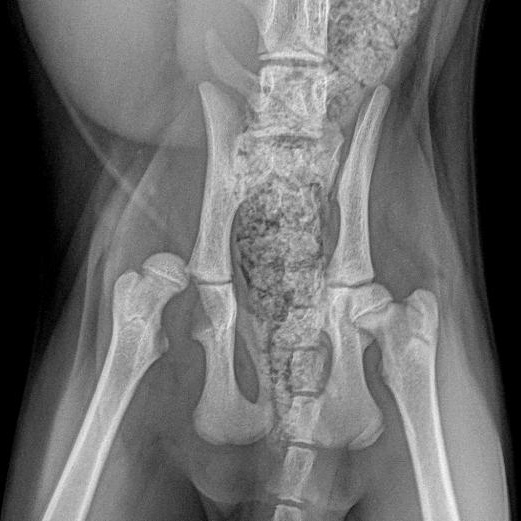

Beanie is a young male cat with a big personality and a whole lot of heart. He came into our care with a sore leg, and after a veterinary exam it turned out he needed major surgery. Beanie bravely underwent FHO surgery and is now recovering like an absolute champ in his foster home.<br/><br/>Despite what he's been through, Beanie is still a happy, social, and playful guy. He’s incredibly friendly, loves people, and tolerates all handling like a pro — including his physio exercises (which he enjoys about as much as any energetic kitten would… but he’s tryin his best!).<br/><br/>Beanie climbs, jumps, and plays as if nothing ever happened. He will always have a bit of limited range of motion in his hind leg — but Beanie never got that memo, and he’s not slowing down anytime soon.<br/><br/>This sweet boy is looking for a home that will cheer him on, keep him active, and appreciate his resilient spirit and affectionate nature. If you’re searching for a fun-loving, social companion with a little extra story behind him, Beanie is ready to curl up and make a permanent place in your heart (and probably your lap).

Beanie is a young male cat with a big personality and a whole lot of heart. He came into our care with a sore leg, and after a veterinary exam it turned out he needed major surgery. Beanie bravely underwent FHO surgery and is now recovering like an absolute champ in his foster home.